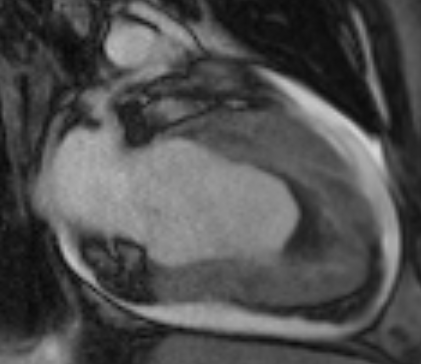

Figure 2; Two Chamber Post Contrast Cine Image Demonstrating Obliteration Of The LV Apex With Thrombus Formation